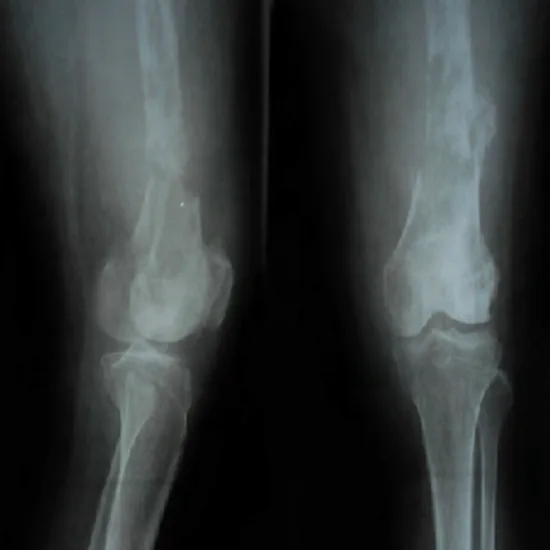

An X-ray of the left femur/ thigh AP/ Lateral View is a non-invasive radiography test that uses radiation to create pictures of the frontal and side view of the femur/ thigh bone and the surrounding soft tissues. The procedure is used to view the femur/thigh for suspected issues such as dislocations, fractures, injury, presence of foreign bodies, and osteomyelitis.

Why is an X-Ray of the Left Femur (Thigh AP/Lateral View) Done?

Doctors prescribe this procedure to assess the Left Femur/ Thigh and detect underlying issues.

• Dislocation of Thigh Bone

• Fracture/ injury to the thigh bone

• Suspected foreign bodies

• Osteomyelitis (An infection in the femur)

• Osteoporosis

• Abnormal growth of thigh bone